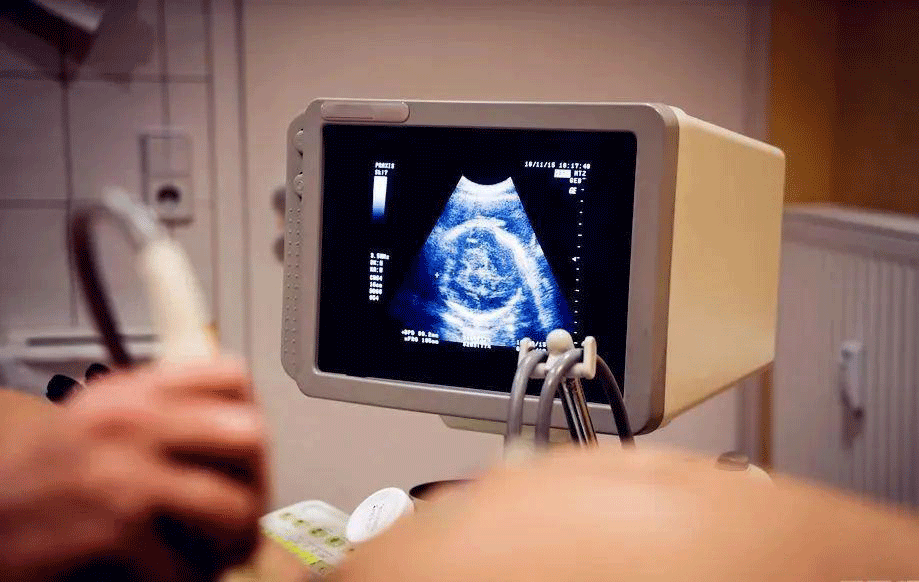

2. 严密监测

• 在促排卵过程中,医生会定期进行超声检查和血液检测,以监测卵泡的发育情况和激素水平的变化。如果发现有过度刺激的迹象,医生会及时调整药物剂量或采取相应的治疗措施。